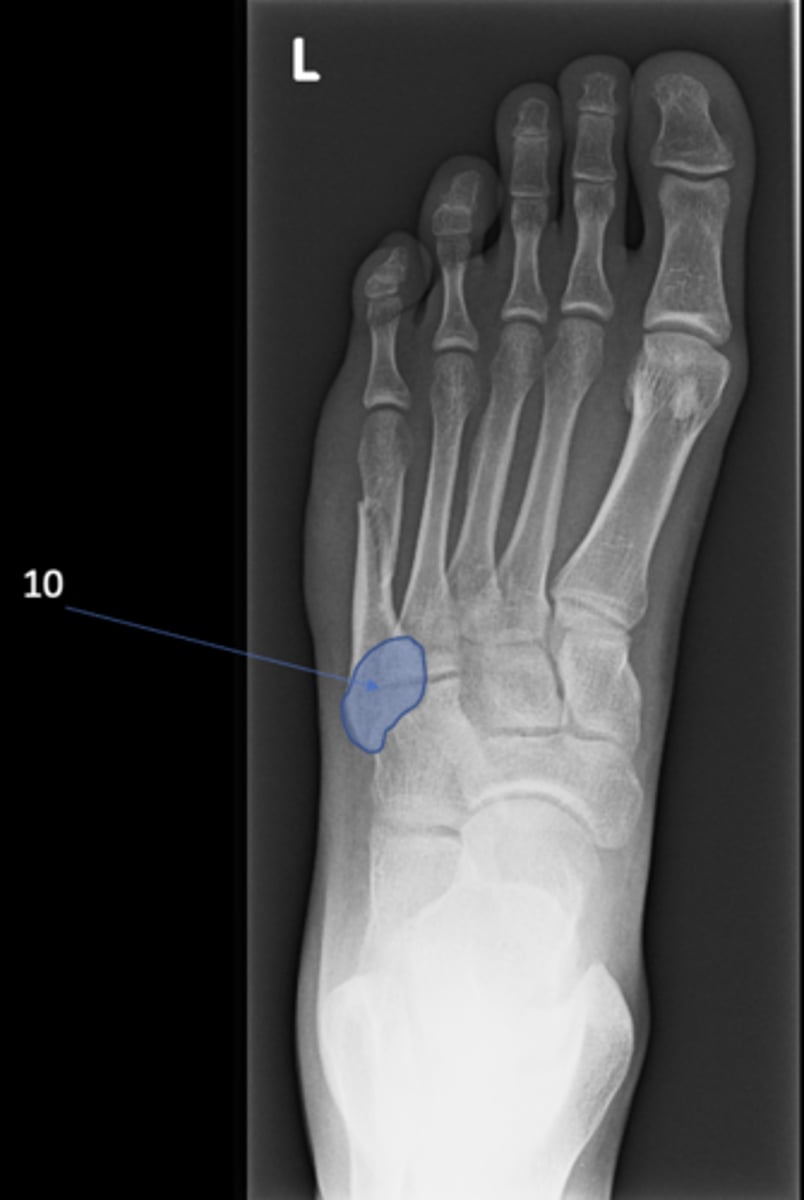

90

Left AP foot

View?

100

Base of 5th metatarsal

ID 10